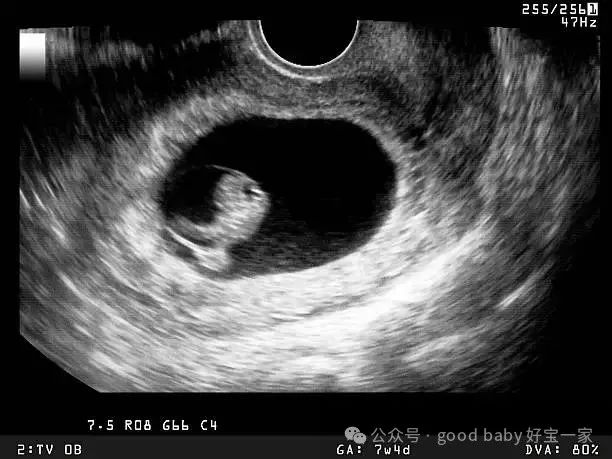

这个时候的胚胎还处在卵裂期,是受精后的第3天。评估鲜胚的等级,主要看以下几点:

第二阶段:发育到第五天、第六天的胚胎,也就是“桑葚胎”或囊胚阶段

这个时候胚胎发育得更成熟了,进入了囊胚期,我们常听到的“4AA”、“4BC”这样的名字,就来自这一阶段的评分系统。